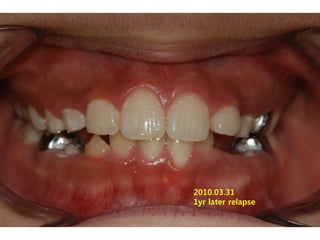

1998.09.25/M

C.C

• Max. protrusion

Dx

• Mentalis action, incorrect tongue posture

Goal

• Establish perioral muscle tone and tongue

posture

2008.08.21   7m

2010.03.31

1yr later relapse